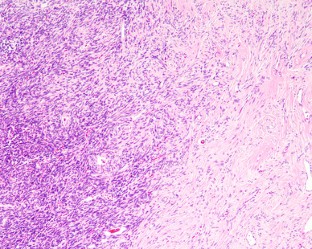

Solitary fibrous tumors (SFTs) are well recognized in the head and neck region, but rarely arise in the sinonasal tract (SNT). Six primary SNT SFTs were identified in the files of Southern California Permanente Medical Group between 2006 and 2017. The patients included five males and one female ranging in age from 33 to 72 years (mean 52 years), most of whom presented clinically with nasal obstruction. Three tumors involved the nasal cavity alone, one involved the paranasal sinuses, and two involved both the nasal cavity and paranasal sinuses. Histologically, the tumors were characterized by a variably cellular proliferation of cytologically bland spindle cells within a collagenous stroma with prominent interspersed branching vessels. Mitotic activity was low (range 0–2 per 10 high power fields) and there was no evidence of pleomorphism or tumor necrosis. Surface ulceration was noted. By immunohistochemistry, the lesional cells were positive for CD34, STAT6 and bcl-2. Clinical follow up information was available for all patients (range 32–102 months; mean 72 months). There were no recurrences or metastases and all were alive with no evidence of disease at last follow-up. SFTs rarely affect the SNT, but should be considered in the differential diagnosis of SNT mesenchymal lesions. Immunohistochemical expression of STAT6 can aid in diagnosis and separation of SFT from other spindle cell lesions occurring at this anatomic site. In combination with cases reported in the literature, primary SNT SFT behave in an indolent manner with conservative treatment.

Fig. 4